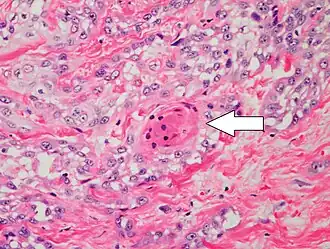

Degree of differentiation

Well-differentiated (yet invasive) cSCC, showing prominent keratinization. It may form pearl-like structures where dermal nests of keratinocytes attempt to mature in a layered fashion. Well-differentiated cSCC has slightly enlarged hyperchromatic nuclei with abundant amounts of cytoplasm. Intercellular bridges will frequently be visible.[12] -

Moderately differentiated lesions of invasive cSCC show much less organization and maturation with significantly less keratin formation.[12] -

Poorly differentiated, where attempts at keratinization are often no longer evident. This is a clear-cell squamous-cell carcinoma. The dysplastic cells infiltrated cords through the dermis. Poorly differentiated cSCC has greatly enlarged pleomorphic nuclei showing a high degree of atypia and frequent mitoses.[12] -

Poorly differentiated clear-cell squamous-cell carcinoma. For this type of cSCC, immunostains will likely be required to classify it unless other areas of the tumor show obvious squamous-cell features, such as seen here (arrow).